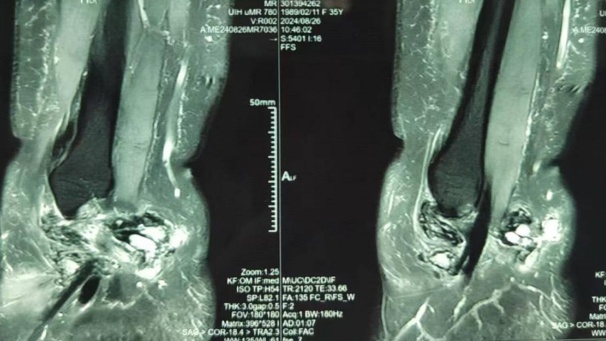

最近马女士觉得疼痛感愈发加重,来到市六医院金山分院诊治,接诊医生在为马女士做了MRI检查后发现,马女士的踝关节里居然有绒毛样的结节状阴影,结合问诊及检查报告等,考虑为左踝关节色素沉着绒毛结节性滑膜炎。

马女士的MRI检查

踝关节MRI上表现为踝关节内局灶性、结节样或弥漫性增生的滑膜,一般无钙化,可呈均匀高密度影,也可有关节囊积液。